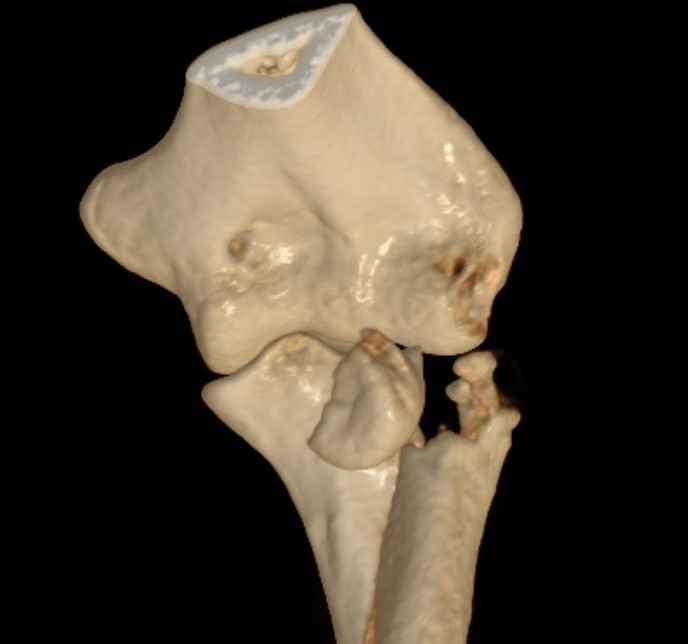

Type 3: Severely comminuted fracture / Non reconstructable

Type 3 radial head fractures